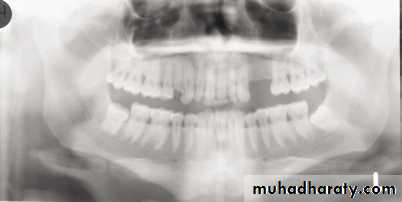

1, Mandibular condyle. 2, Articular eminence. 3, Coronoid process of mandible superimposed on zygomatic arch. 4, Posterior wall of maxillary sinus. 5, Posterior wall of zygomatic process of maxilla. 6, Hard palate. 7, Nasal septum. 8, Tip of nose. 9, Dorsum of tongue. 10, Hyoid superimposed over inferior border of mandible. 11, Inferior border of maxillary sinus. 12, Image of cervical spine. 13, Medial border of maxillary sinus. 14, Infraorbital canal. 15, Infraorbital rim. 16, Pterygomaxillary fissure. 17, Anterior border of the pterygoid plates. 18, Lateral pterygoid plate superimposed over soft palate and coronoid process of mandible. 19, Ear lobe. 20, Inferior border of mandibular canal. 21, Mental foramen. 22, Posterior wall of nasopharynx. 23, Inferior border of mandible superimposed from opposite side. 24, Soft palate over mandibular foramen of mandible.

Panoramic Radiography